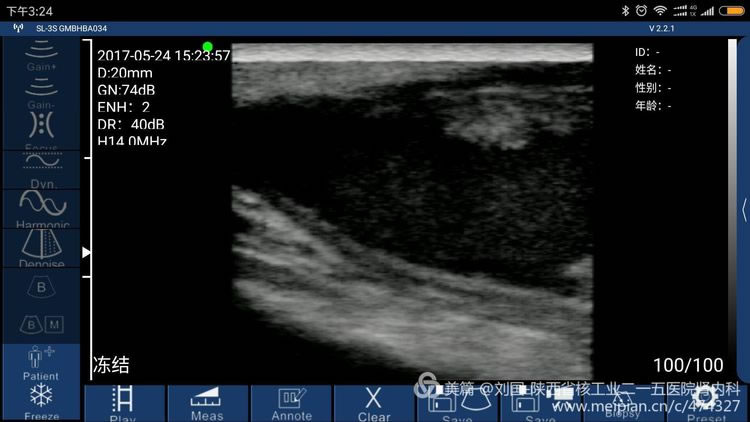

The patient’s barchial artery was punctured in error by a nurse of some hospital’s blood purification center, which caused large area of his arm was bruising and his arm swells, covering up doctors and nurses’ awareness, not to find out mistaken puncture timely and barchial artery’s crevasse, and not to timely oppress the barchial artery effectively. Till the bruising was totally dispersed, the swell faded away, part of the below gradually enlarged to impact the forearm buckling. After he saw a doctor in our hospital, I found I could heard hemokinesis sound. Pseudoaneurysm of elbow brachial artery with 3mm-crevasse was confirmed by ultrasound.

Result checked by Sonostar’s wireless ultrasound, and displayed by my mobile phone-Mi max

Sonostar’s True Features